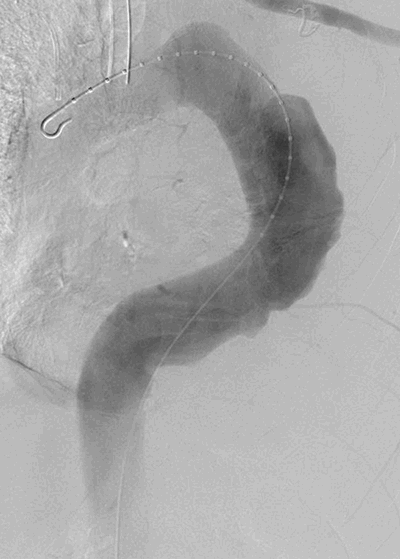

Upon placement, there was immediate brisk and bright red blood return from the catheter as well as transient hypotension that responded to a saline bolus. The catheter was clamped, and a post-procedure non-contrasted CT of the chest confirmed catheter placement within the aneurysm sac of his known TAAA. The patient remained hemodynamically stable after the initial transient drop in blood pressure and was transferred emergently to our institution. A 1 mm slice CTA was obtained for better anatomical detail, three-dimensional reconstruction, and centerline measurements in the event that aortic repair would be required (Figure 2 and Figure 3). At the site of chest wall entry, the aneurysm sac was immediately adjacent to the posterior chest wall. The catheter was primarily traversing organized, mural thrombus, but the curved distal tip was just within the patent lumen.

Figure 2. Axial CT angiogram chest demonstrating pigtail catheter visible in TAA sac with no active extravasation of contrast. Arrow indicates catheter.